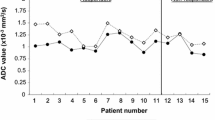

In the spectra obtained from our uterine cervical tumours, it was possible to identify the signals of Glx, m-Ins, tCho, tCr, NAA, Ala, Lac, and Lip, as shown in Fig. 1a. Quantification was obtained for those metabolites who satisfy the condition of Cramer-Rao lower bounds less than 20% and therefore for tCho, Glx, NAA, and Lip. Short TE (28 ms) spectra presented a different metabolic pattern in the two populations GR and NR/PR. In particular, as a first result, we observed that the mean Lip value in GR patients (100 ± 50 mM) was significantly lower than in PR-or-NR patients (270 ± 50 mM) (p = 0.040). Representative spectra are shown in Fig. 1a (low lipid level, L) and Fig. 1d (high lipid level, H). Long TE (144 ms) spectra analysis showed absence or low level of Lac at 1.3 ppm, thus excluding lipid overestimation in the quantitative analysis.

Representative spectra (echo time 30 ms) of the two groups: (a) low and (d) high lipid level, corresponding to good responder patients (GR) and partial or nonresponder patients (PR-or-NR), respectively. Peak assignments: Glx, Glutamine plus glutamate; m-Ins, Myo-inositol; tCho, GPC plus PCho or total choline; tCr, Creatine plus phosphocreatine; Ala, Alanine; Lip, Lipids; Lac, Lactate. T2-weighted paraaxial (b, e) and sagittal (c, f) images of the two cases

Moreover, a significant difference was also observed in tCho distribution. In the GR group, the mean tCho peak value (4.2 ± 1.9 mM) was significantly higher than in the PR-or-NR group (1.8 ± 0.4 mM) (p = 0.040). Finally, we also observed a significant difference in the Lip/tCho ratio with higher values in PR-or-NR patients (30 ± 20) than in GR patients (160 ± 60) (p = 0.040). Figure 2 shows the box plots of the signals of Lip (a), tCho (b) and of the ratio Lip/tCho (c), and Table 3 summarises the data obtained.